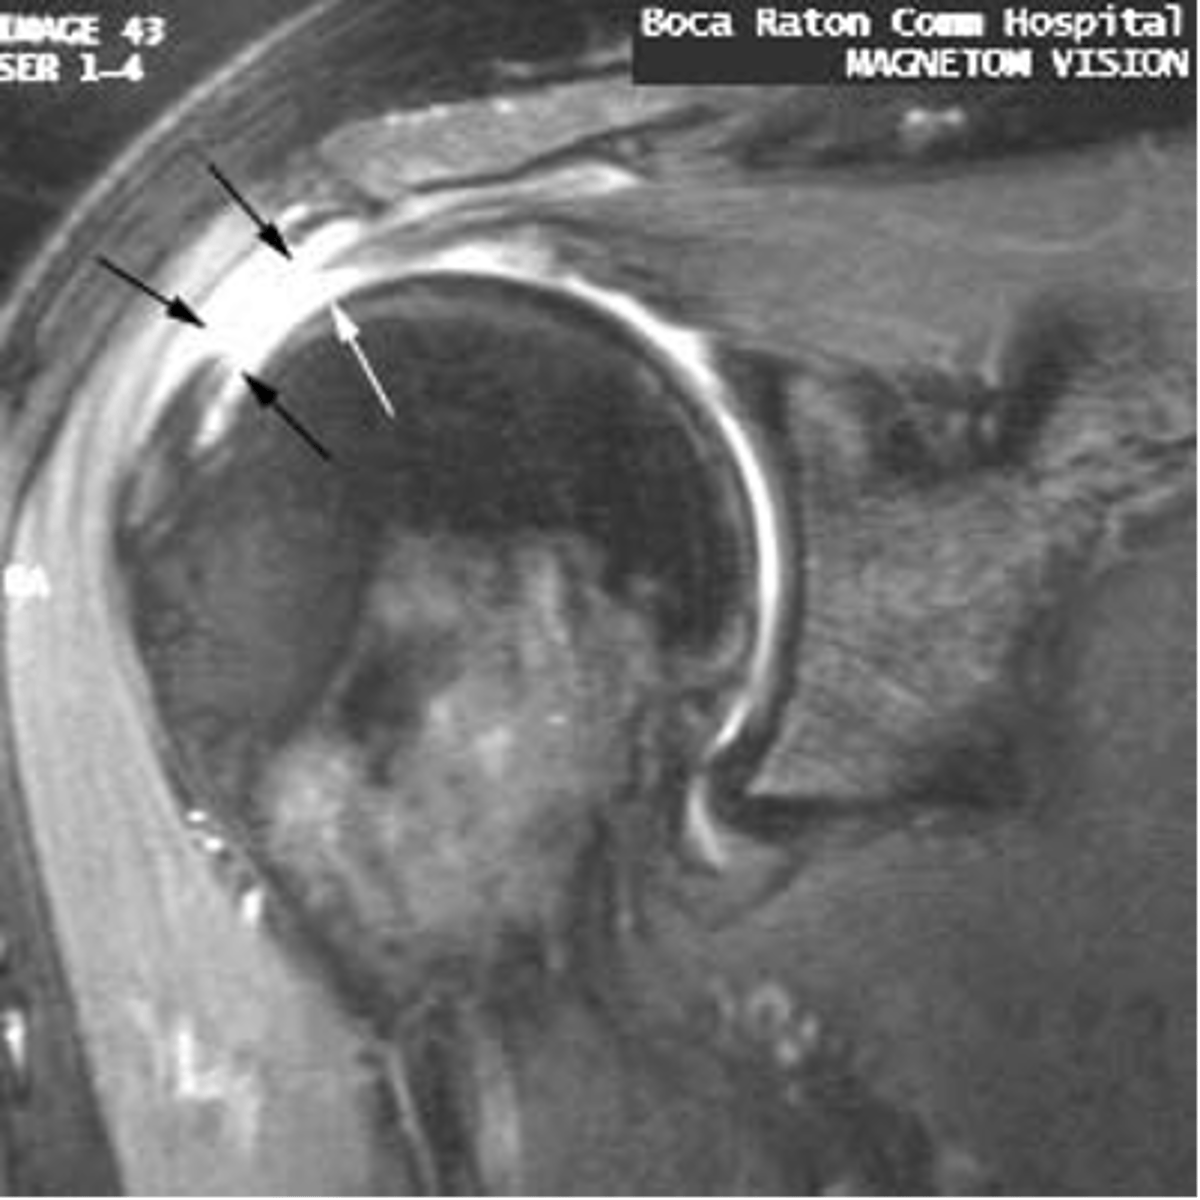

Full-thickness tear!!

- fluid (area of tear) in white

- retraction in red

- bucking in green

What is this image depicting w/ the rotator cuff? (hint: it is a T2 image)